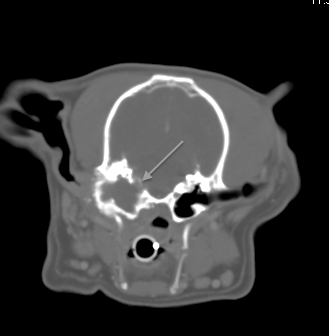

Fig 2:

Transverse CT of the same dog in Fig1 showing erosion into the cranial vault and meningeal enhancement (meningitis)